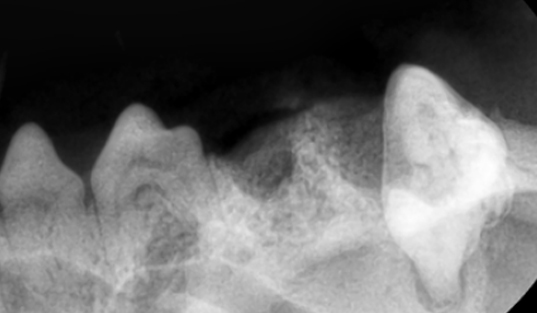

치아 흡수성 병변 (FORL)은 고양이의 치아가 자연스럽게 녹아서 흡수되는 질병입니다. 원인은 다양하지만, 일반적인 임상증상으로는 식욕부진, 잇몸 염증, 유연(침흘림), 통증, 씹지 않고 삼킴, 부드러운 음식 위주의 식이 등의 증상을 보이며 유형별로 흡수되는 위치가 달라, 눈으로 안보이는 경우가 많습니다. 내원 당시에 치아가 흡수되어 안보이는 경우도 있으며 이미 흡수가 시작된 치아의 경우 내과적인 치료만으로는 치료가 제한되고 밥을 잘 먹지 못할 정도의 통증이 동반되어 치과방사선 촬영으로 뿌리가 어느정도 흡수 되었는지, 부러진데는 없는지 육안상으로 보이지 않는 부분까지 꼼꼼히 확인한 후 발치를 진행합니다. 한쪽에 생기는 경우, 반대편에도 잘 생기기에 정밀한 치과방사선 촬영이 필요합니다.